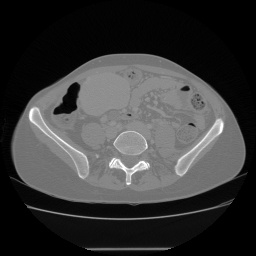

由于医学影像的独特属性,在大多数情况下其详细数据不会被广泛分享。现将一个公开获取的数据库——3D-IRCADB介绍如下:该数据库包含来自20名患者的CT扫描图像序列;具体而言,每个患者大约拥有几百张左右的扫描图像。这些扫描通常以 DICOM 格式存储;此外,在进行深度学习分析时,默认也会使用对应的掩膜(mask),这些掩膜同样采用 DICOM 格式存储。为了便于后续处理和分析,在此将原始 DICOM 格式的图像转换为 PNG 格式保存;长图:image:

label: